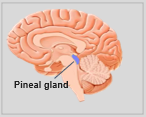

Neuroanatomie is de tak van de anatomie die de anatomie van het zenuwstelsel bestudeert, dat wil zeggen de structuur, functie en organisatie van het zenuwstelsel. Het zenuwstelsel is een van de meest complexe systemen in het menselijk lichaam en omvat de hersenen, het ruggenmerg, perifere zenuwen en zenuwganglia. Neuroanatomie houdt zich bezig met hoe deze structuren met elkaar verbonden zijn, hoe signalen tussen zenuwcellen worden doorgegeven en hoe de verschillende delen van het zenuwstelsel samenwerken om lichamelijke en cognitieve functies te besturen. Neuroanatomen maken gebruik van geavanceerde beeldvormingstechnieken, zoals MRI (magnetic resonance imaging), PET (positron emission tomography) en microscopie om de structuren en functies van het zenuwstelsel te visualiseren.